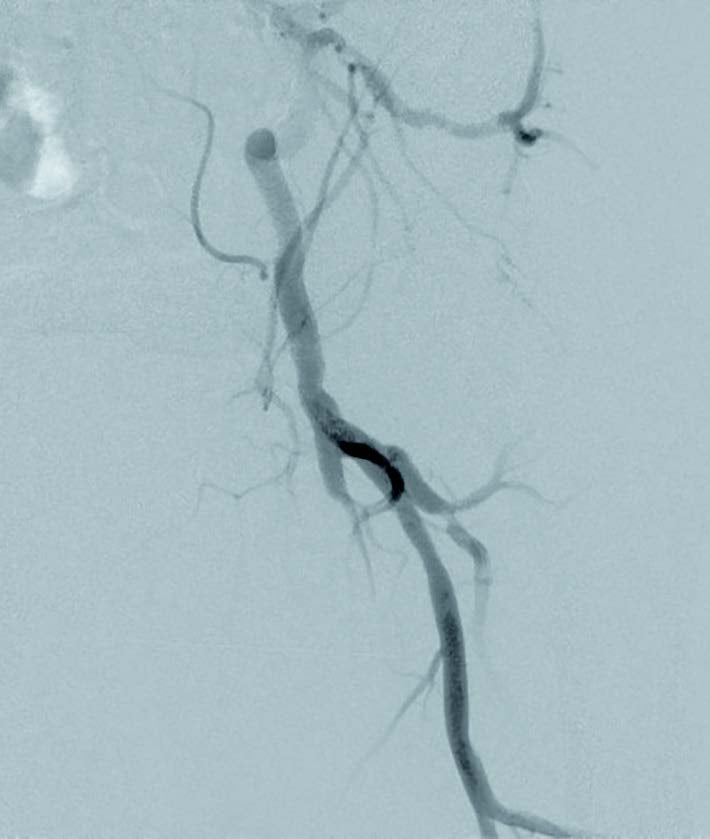

前拡張後の造影で温存したいコラテ部分に解離が認められ(図2)、また、IVUSでヘルシーランディングが可能な位置を確認したところ、遠位部のコラテ(図1矢印②)を温存してヘルシーランディングができることを確認できた。さらにIVUSで血管径を確認し、同等サイズのバイアバーン® ステントグラフトを留置した。バイアバーン® ステントグラフトが展開し始めた後、展開ラインをゆっくり連続した動作で引くようにするとバイアバーン® ステントグラフトの位置がずれることなく留置することが可能であった。その後、バイアバーン® ステントグラフト全長を同径のバルーンで高圧後拡張してIVUSでバイアバーン® ステントグラフトが充分拡張されていることを確認し、手技を終了した。(図3)

実際、前拡張に径6.0 mmのロングバルーンを用いて長時間拡張を行ったところ造影上、長い解離が明らかで、IVUS上もプラークの圧縮は不充分であった。ベアメタルステントでの長期予後が期待できないこと、薬剤コーティングバルーン(DCB)を使用するには解離が大きいことや保険償還の観点から、当症例でのデバイス選択としてはバイアバーン® ステントグラフトが長期予後を期待できると考えた。

当症例は比較的石灰化の少ない長区間のCTO症例であり、臨床成績の観点や長さ20 cm以上の病変に対しても薬事適応が認められているデバイスであるという観点もふまえて、バイアバーン® ステントグラフトを選択した。当症例において、IVUS所見からは血管径が6.0 mmあり小血管ではないことや、留置位置となるレファレンス上下ともヘルシーランディングが可能かを確認したうえで、バイアバーン® ステントグラフトを留置した。コラテラル血管の温存が悩ましい症例であったが、より遠位部のコラテラル血管も温存できることもあり、ヘルシーランディングを重視し、コラテ血管をバイアバーン® ステントグラフトでカバーし、病変をフルカバーすることで再狭窄の懸念も少なく、長期予後を期待できると考えた。

また、デバイス留置に際しても、上下の位置をピンポイントで決めて留置しやすく、留置位置がずれる心配が少ないこともバイアバーン® ステントグラフトの魅力の一つであると考える。